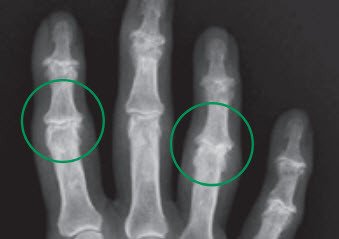

Es handelt sich häufig um eine Blickdiagnose: Die Mittel- und Endgelenke der Finger sind geschwollen und spindelförmig aufgetrieben, die Endgelenke weisen manchmal eine typische Knotenbildung auf. Teilweise kommt es auch zu einer leichten Achsabweichung im betroffenen Gelenk. Eine gezielte Röntgenaufnahme kann die Diagnose bestätigen. Zusätzliche Untersuchungen sind in der Regel nicht notwendig.

Arthrose an den Fingergrund- und Fingermittelgelenken

Die Fingergrund- und -mittelgelenke stellen wichtige Elemente in der Gesamtbeweglichkeit eines Fingers dar. Wenn immer möglich bevorzugen wir deshalb einen bewegungserhaltenden Eingriff. Dabei haben sich Silikonkunstgelenke als präferierte Wahl herausgestellt – sie bewähren sich seit über fünfzig Jahren sehr gut. Mit dem Kunstgelenk bleibt eine gewisse Beweglichkeit erhalten, was zusammen mit der Schmerzbefreiung eine erhebliche Verbesserung der Lebensqualität für den Patienten bedeutet.

Neuentwicklungen als Oberflächenersatz (ähnlich einem Kunstgelenk für ein Knie) zeigen ebenfalls vielversprechende Resultate mit einer gegenüber Silikon verbesserten Stabilität. Deren Einsatz ist jedoch nur bei guter Knochenqualität möglich und muss im Einzelfall besprochen werden.